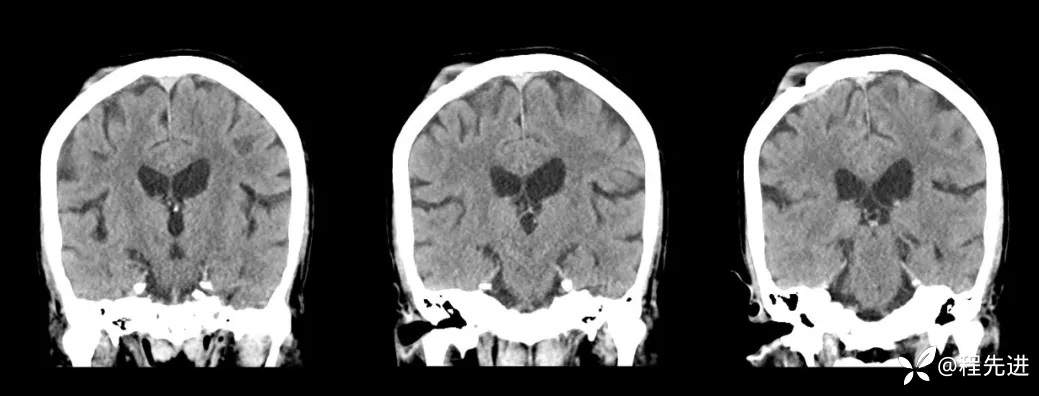

【现病史及既往史】:体检发现胰尾部肿块4年,当时手术病理提示异常增生性病变,现发现右侧顶部包块,逐渐增大,无明显感觉不适

查体:右侧顶部皮下可触及一包块,长约23mm,压痛(+),波动感(+-),可推动,边界清晰。

影像检查: